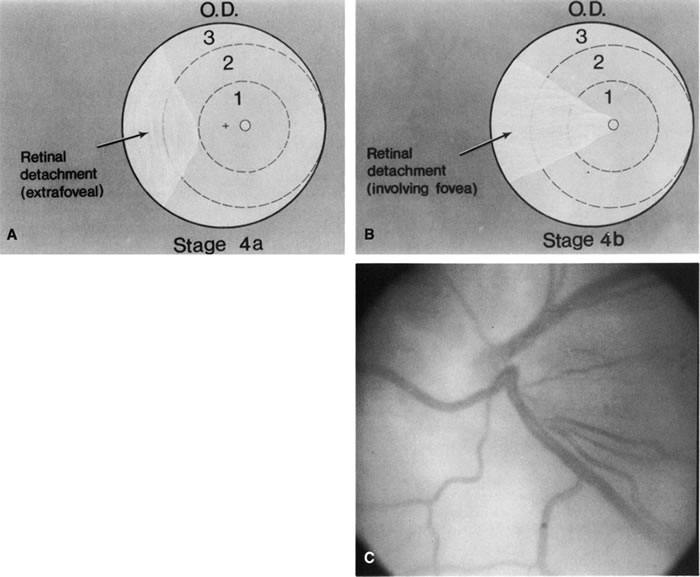

for the Classification of the Late Stages of Retinopathy of Prematurity. Arch Ophthalmol 105:906, 1987. 60a. Capone A Jr, Trese MT: Lens-sparing vitreous surgery for tractional stage 4A retinopathy

of prematurity retinal detachments. Ophthalmology 108:2068, 2001 61. Gilbert WS, Quinn GE, Dobson V et al: Partial retinal detachment at 3 months after threshold retinopathy of prematurity. Long-term structural and functional outcome. Multicenter Trial of Cryotherapy for Retinopathy of Prematurity Cooperative

Group. Arch Ophthalmol 114:1085, 1996 62. Trese MT. Scleral buckling for retinopathy of prematurity. Ophthalmology 101:23, 1994 63. Hinz BJ, de Juan E Jr, Repka MX: Scleral buckling surgery for active stage 4A retinopathy of prematurity. Ophthalmology 105:1827, 1998 64. Chuang YC, Yang CM: Scleral buckling for stage 4 retinopathy of prematurity. Ophthalmic Surg Lasers 31:374, 2000 65. Choi MY, Yu YS: Efficacy of removal of buckle after scleral buckling surgery for retinopathy